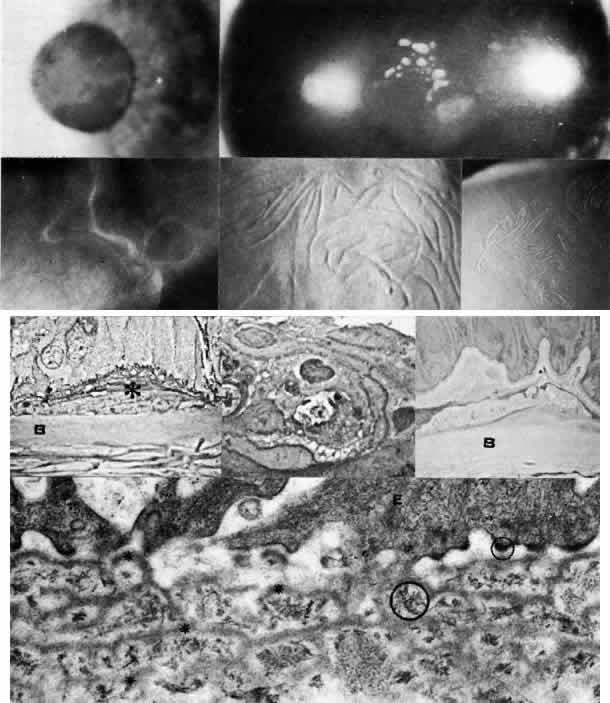

Granular Dystrophy (Groenouw Type I)

Granular dystrophy is manifested in the first decade of life and is transmitted as an autosomal dominant trait. The lesions are sharply demarcated, milky, opaque figures resembling snowflakes or bread crumbs and are confined to the axial portion of the cornea, usually beginning in the most superficial portion of the stroma (Figs. 5 AND 9; Color Plate 1F). During their evolution, they may extend more posteriorly. Between the dense opacities the intervening cornea is characteristically clear. Variants with confluent central opacities and epithelial involvement have been described.98

Fig. 9. Granular corneal dystrophy. Top left. Discrete, large opacities predominantly affect the central stroma. Top right. Retroillumination emphasizes the optical clarity of intervening stroma between granular opacities. Middle left. Light microscopy of hyaline deposits is accentuated with Masson trichrome stain (× 250). Right. Transmission electron micrograph shows relatively normal epithelium (E) and basement membrane (arrowheads) anterior to large electron-dense deposits (*) within Bowman's layer and stroma (× 4,500). Bottom left. Higher magnification transmission electron micrograph of granular deposits shows characteristic rod-shaped paracrystalline structure ( × 50,000). (Top right, Slit lamp photograph courtesy of Lawrence Hirst, MD)

Jones and Zimmerman99 noted the opacities to consist of areas of hyaline degeneration in which stromal fibers appeared “granular.” Histologically, the deposits stain red with Masson trichrome stain and are less PAS-positive and less birefringent than the normal stroma. Numerous argyrophilic fibers are seen on Wilder's reticulin stain. Using histochemical techniques, Garner100 concluded that the deposits consisted mainly of noncollagenous protein containing tryptophan, arginine, tyramine, and sulfur-containing amino acids, and he postulated that the abnormal proteins originated from the epithelium, keratocytes, and extracorneal sources. Rodrigues and co-workers101 found immunofluorescent evidence of microfibrillar protein, a poorly characterized glycoprotein, as well as a Luxol fast blue-staining phospholipid. Johnson and co-workers suggest an epithelial origin of the deposits based on light and electron microscopic studies of corneas with recurrent granular dystrophy.102 On transmission electron microscopy, the deposits appear as extracellular, rod-shaped, electron-dense paracrystalline structures with faintly visible periodicity. Keratocytes, endothelium, and Descemet's membrane appear unaffected.103

Lattice Dystrophy

Lattice dystrophy is an autosomal dominant condition characterized by pathognomonic, branching “pipestem” lattice figures within the stroma (Figs. 5 AND 10; Color Plate 1G). Symptoms usually begin in the first decade of life and include decreased vision as well as recurrent erosions because of subepithelial and stromal accumulations of amyloid material. In time, the condition progresses to involve marked opacification of the axial stroma, as well as in the superficial layers, leaving the limbus relatively free. At this stage, since the cornea also shows a superficial haze, it becomes difficult to visualize typical lattice lesions, and hence examination of younger affected family members is useful. Amyloid accumulation under the epithelium gives rise to poor epithelial-stromal adhesion with consequent recurrent erosion syndrome.49 The dystrophy advances inexorably, and by age 40 or earlier these problems become markedly aggravated, causing considerable discomfort and visual incapacity.

Fig. 10. Lattice corneal dystrophy. Top. Slit lamp photograph demonstrates pathognomonic branching lattice figures throughout the stroma. Middle left. Phase-contrast photomicrograph shows subepithelial accumulations of fibrillar amyloid deposits (*) causing distortion of epithelial contour. B, Bowman's layer (paraphenylenediamine, × 800). Middle right. Transmission electron micrograph of basement membrane complexes reveals basement membrane irregularity and discontinuity resulting from underlying amyloid fibrils (× 21,000). Bottom left. Transmission electron micrograph of stroma shows normal collagen fibrils and keratocytes with electron-dense material abnormally dispersed extracellularly (× 16,000). Bottom right. High-magnification transmission electron micrograph resolves lattice material as masses of fine, 8- to 10-nm diameter amyloid fibrils (circled below) in comparison with larger-size stromal collagen fibrils (above) (× 75,000). (Slit lamp photographs courtesy of WJ Stark, MD)

Many published reports have documented the nature of the corneal deposits in lattice dystrophy. In 1961, Jones and Zimmerman99 and others suggested that the disorder was due to amyloid degeneration of the stromal collagen fibers. In 1967, Klintworth111 confirmed that the disorder was a familial form of amyloidosis limited to the cornea and showed that the fibrillar material stained with Congo red and exhibited the birefringence and dichroism typical of amyloid. On transmission electron microscopy, the fine, electron-dense fibrils of 8 to 10 nm diameter are similar to those of known amyloid fibrils. Using fluorescence microscopy, staining with thioflavin-T is helpful in further characterizing the amyloid material, as are immunofluorescent studies using antihuman amyloid anti-sera.112 Evaluation of corneas with typical lattice dystrophy has demonstrated the presence of the amyloid P (AP) component, but staining for amyloid A (AA) protein has remained controversial.113–117 The corneal endothelium and Descemet's membrane are not involved. Moreover, amyloid deposits have not been found in other excised tissues from patients with typical lattice dystrophy.111

The specific etiology of the amyloid deposits is, as yet, unclear. They may be secondary to collagen degeneration, perhaps from lysosomal enzymes elaborated by abnormal keratocytes. An alternative theory holds that abnormal keratocytes actually produce the abnormal amyloid substance, although this process is not ultrastructurally evident.

Macular Dystrophy (Groenouw Type II)

Among the classic corneal dystrophies, macular dystrophy, unlike granular and lattice dystrophies, is an autosomal recessive disorder and is far less common. It usually begins in the first decade of life and leads to progressive visual deterioration as the stroma becomes generally cloudy, with superimposed dense, gray-white spots (Figs. 5 AND 11; Color Plate 1H). Unlike granular dystrophy, these macular spots have indefinite edges and the intervening stroma is not clear. Young patients exhibit axial lesions in the superficial layers of the cornea, but with time, lesions approach the periphery and extend throughout the entire stromal thickness. Corneal thinning confirmed by central pachymetry has been documented.129 Also unique is primary involvement of the endothelium as evidenced clinically by the presence of guttate changes of Descemet's membrane.

Fig. 11. Macular corneal dystrophy. Top left. Clinical appearance of cornea features diffuse haze extending to the limbus with superimposed, dense gray-white spots. Bottom left. Light photomicrograph of posterior cornea shows endothelial cells staining intensely positive for acid mucopolysaccharide. Guttate excrescences (*) of Descemet's membrane (DM) are frequent. The stroma also shows positive staining for acid mucopolysaccharide both diffusely extracellularly and intensely within keratocytes (circled) (colloidal iron × 500). Right. Transmission electron micrograph discloses typical fibrillary granular deposits within keratocytes (K), throughout the posterior layer of Descemet's membrane, and within the endothelial cells (En). The anterior banded region of Descemet's membrane (bracketed) is not affected (× 3500).

The lesions in macular corneal dystrophy stain intensely with alcian blue and colloidal iron, minimally with PAS, and not at all with Masson's trichrome. Birefringence is decreased. The lesions have been histochemically identified as an abnormal keratan sulfate-like glycosaminoglycan that accumulates extracellularly within the stroma and Descemet's membrane and intracellularly within keratocytes and endothelium.130

As would be typical of an autosomal recessively inherited condition, macular dystrophy presumably results from deficiency of a hydrolytic enzymes (sulfotransferase) and may thus be considered a localized mucopolysaccharidosis.131 The effect of altered glycosaminoglycan metabolism is evident at the cellular level; on transmission electron microscopy, keratocytes and endothelial cells exhibit distention of rough-surfaced endoplasmic reticulum cisternae. With the acridine orange technique, compensatory generalized hyperactivity of the lysosomal enzyme system has been demonstrated.132 Eventually the accumulated undigested storage products engorge the cells, and the cells ultimately degenerate or rupture. The derivation of these intracytoplasmic storage vacuoles from endoplasmic reticulum suggests that the biochemical lesion in macular dystrophy occurs at a different metabolic location than in the systemic mucopolysaccharidoses, since in the latter, storage products accumulate within lysosomelike intracytoplasmic vacuoles associated with the Golgi complex.133 Snip and associates134 were able to determine that the storage phenomenon affecting endothelium and Descemet's membrane is likely also primary, since the intracellular and extracellular lesions appear ultrastructurally comparable to those evident in the keratocytes and stroma.